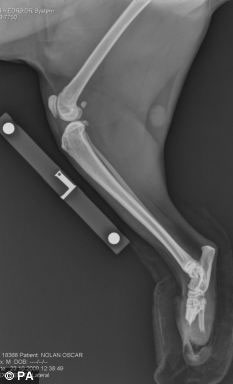

手術前貓腿X光照片

接受手術的這只貓叫奧斯卡,今年2歲,9個月前,在一次事故中它的兩只后爪被聯合收割機切斷,險些喪生。正常情況下,3條腿的貓還能正常生活,但2條腿的貓就不行了。

菲茨帕特里克醫生說:“我們只能給它裝新腿,否則只能實施安樂死。但還沒人做過這樣的手術?!贬t療團隊研究了鹿角如何生長,根據這個原理,他們把兩個特制的含鈦及其它成分的金屬棒,釘入奧斯卡的后腿。然后在金屬棒的末端安上仿生爪子。不過,奧斯卡以后只能在室內活動,因為這種假肢不合適戶外的環境。